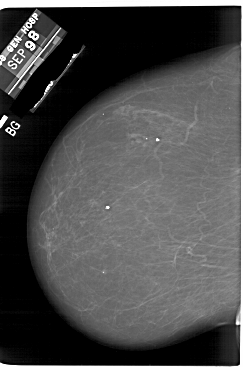

A_1850_1.LEFT_MLO

LEFT_CC LINES 6601 PIXELS_PER_LINE 4366 BITS_PER_PIXEL 12 RESOLUTION 43.5 NON_OVERLAY